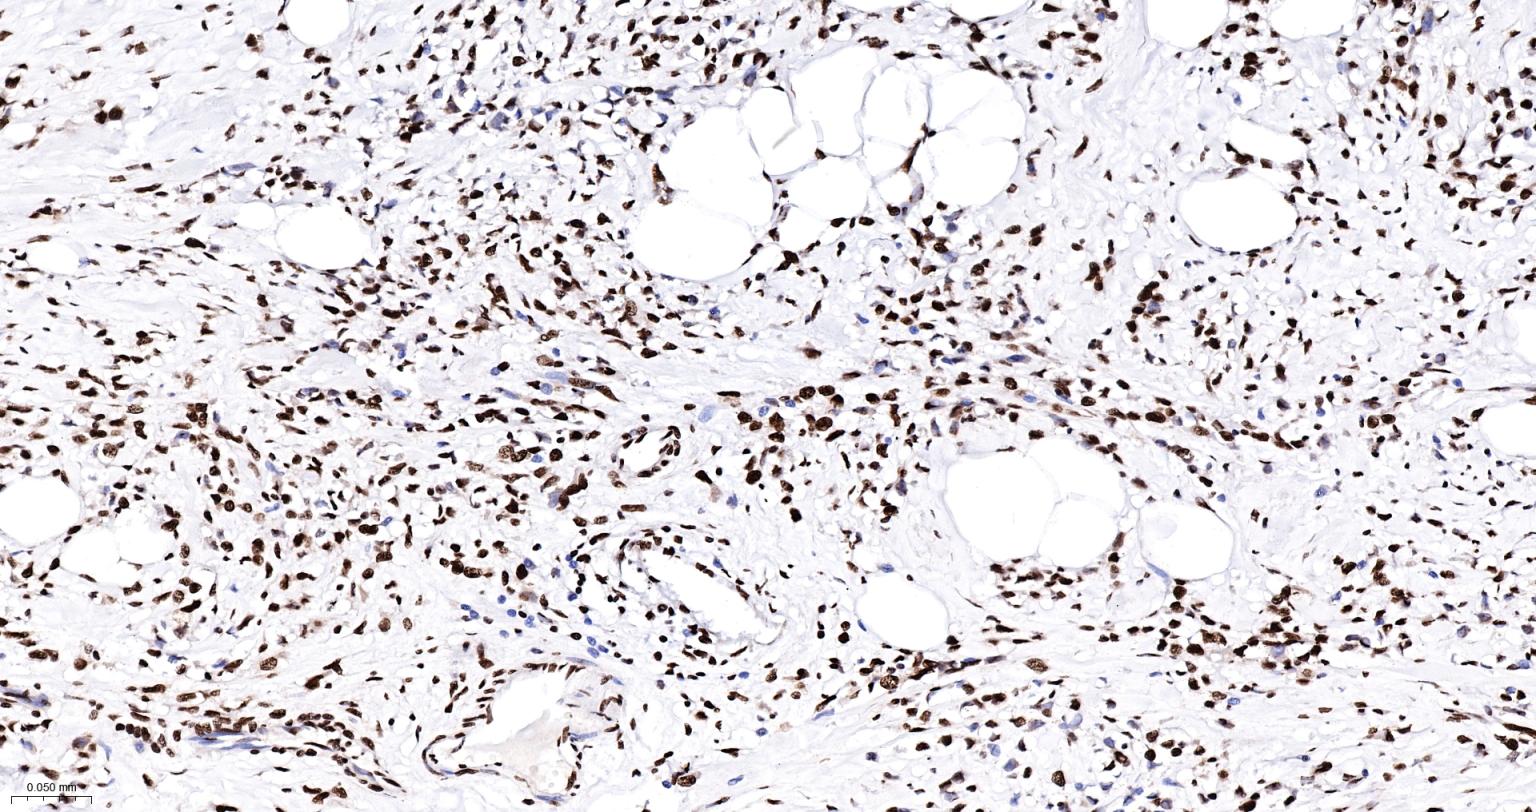

Paraformaldehyde-fixed, paraffin embedded Human Breast Cancer; Antigen retrieval by boiling in sodium citrate buffer (pH6.0) for 15 min; The section was incubated with Cortactin Monoclonal Antibody, Unconjugated (bsm-61251R) at 1:200 overnight at 4°C, followed by conjugation to the bs-0295G-HRP and DAB (C-0010) staining.